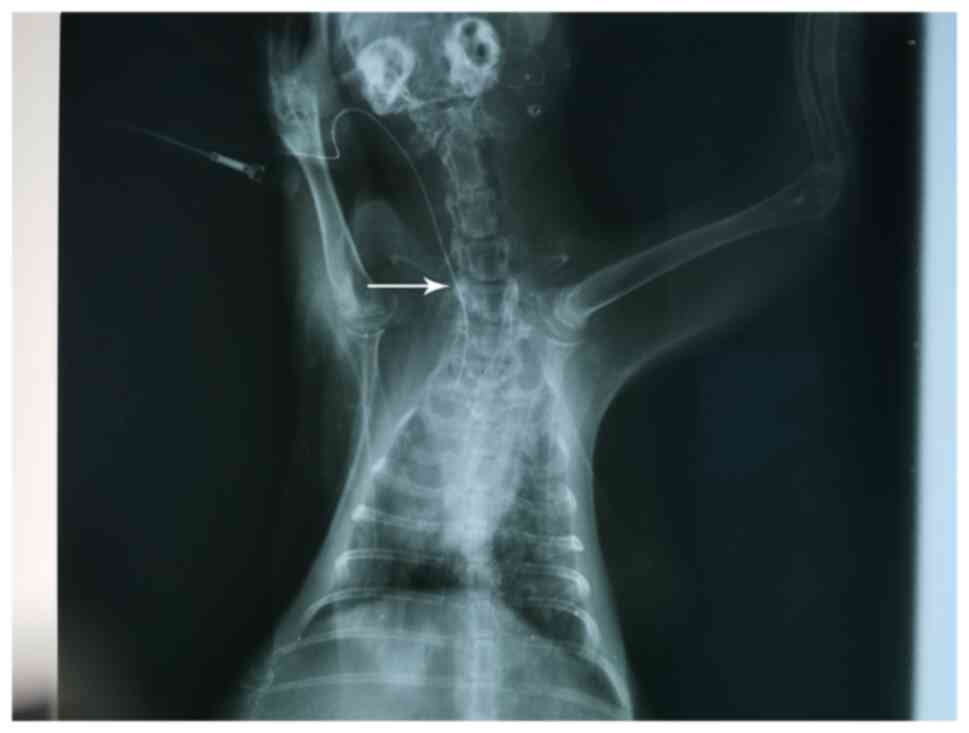

Evaluation of PICC models

The criteria for evaluating the successful establishment of PICC models were as follows: i) The established animal model of PICC was successful with one puncture; ii) there was no local damage or bleeding in the puncture; iii) the end of the catheter was not twisted or folded under X-ray fluoroscopy; and iv) the PICC tube was placed in the anterior vena cava. As presented in Fig. 2, the transparent dot corresponded to the end of the catheter.

Figure 2

X-ray fluoroscopy of the PICC tube. X-ray demonstrated that the end of the PICC tube reached the anterior vena cava of the rabbit. Arrow indicates the transparent dot that highlights the end of the catheter. PICC, peripherally inserted central catheter.

Construction of a PICC chemotherapy rabbit model

In the present study, a PICC chemotherapy model was successfully established in 48 rabbits. To observe the pathological changes of the puncture point during PICC catheterization, the rabbits were randomly separated into eight experimental groups. A course of chemotherapy includes 2-3 cycles (19); the present study was based on two cycles. X-rays were captured to confirm that the end of the catheter was not twisted or folded, and was placed in the anterior vena cava (Fig. 3). In each group, the local puncture site displayed no injury or bleeding. Thus, it was determined that the PICC models were successfully constructed.

Figure 3

X-ray imaging determination of successful peripherally inserted central catheter model construction. The end of the catheter was not twisted or folded, and it was placed in the anterior vena cava. Arrow indicates the catheter.